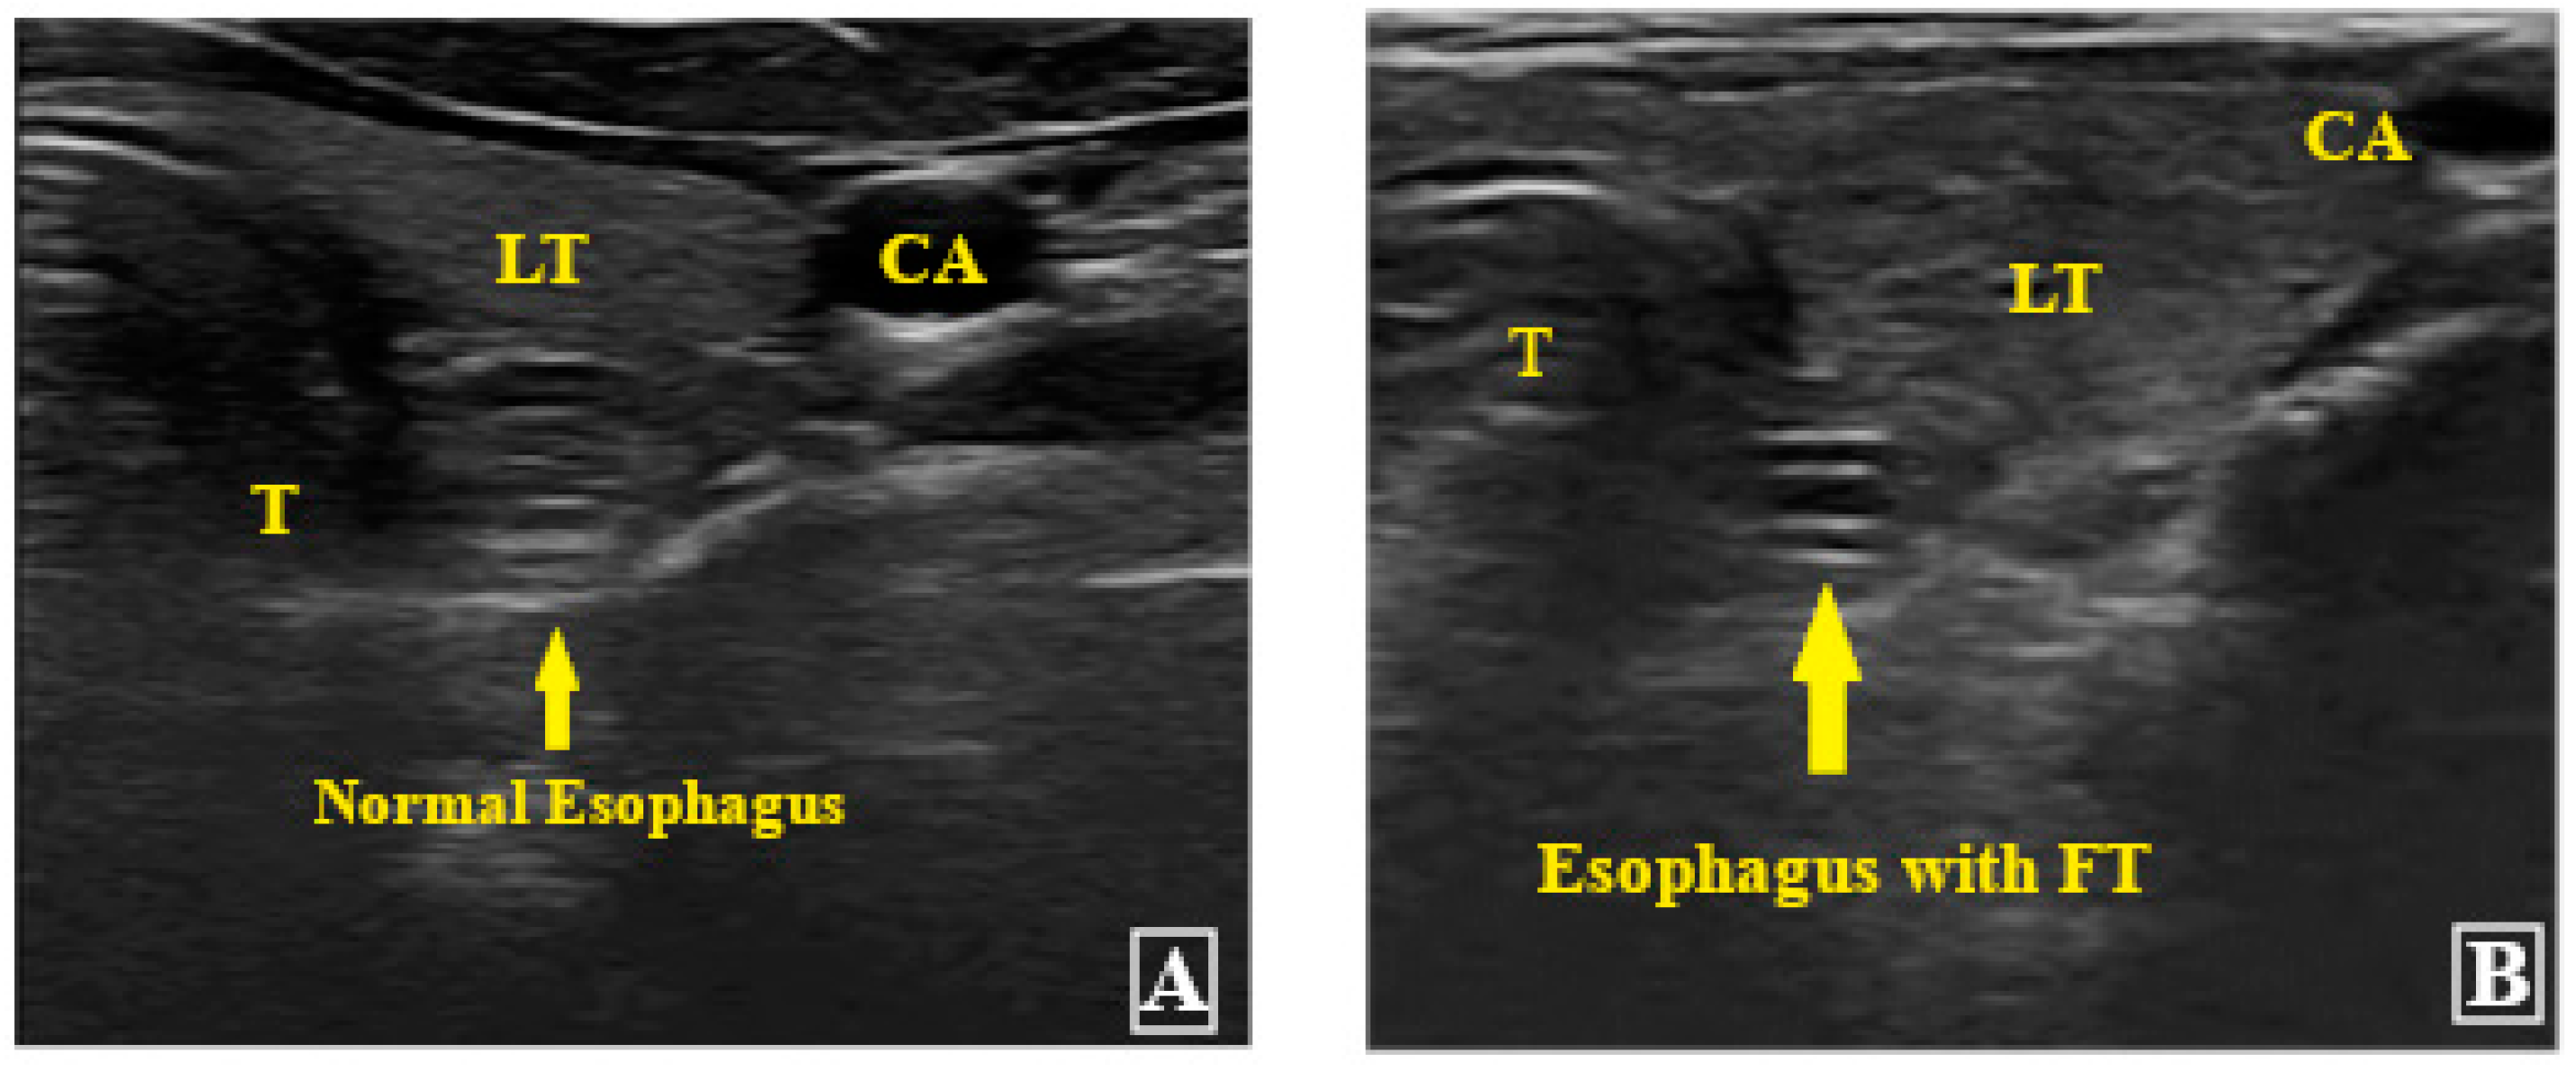

2. Materials and Methods